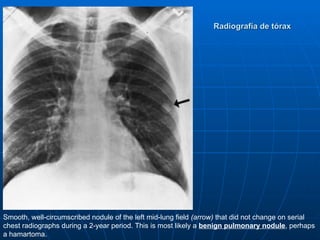

Radiografía de tórax

Smooth, well-circumscribed nodule of the left mid-lung field (arrow) that did not change on serial

chest radiographs during a 2-year period. This is most likely a benign pulmonary nodule, perhaps

a hamartoma.